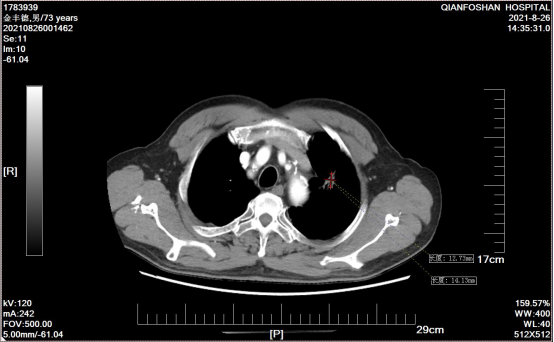

患者氩氦刀治疗结合正规化疗,复查肿瘤持续缩小

经过再次病理检查,李老伯患的确是肺鳞状上皮细胞癌,所以氩氦刀治疗后仍需定期复查,并进行正规化疗。根据刘元水的意见,李老伯每3-4个月回来复查,调整治疗方案,期间可以按照治疗方案在当地医院进行治疗。就像一个约定,此后4年,李老伯风雨无阻,定期从商河赶到山一大一附院复诊。肿瘤微创科医生魏有国介绍说,“患者左肺肿瘤逐渐缩小,病情稳定、治疗过程也很顺利。”四来年,魏有国作为李老伯的主管医师,一直负责他的治疗。“太感激刘主任和魏大夫了,是他们帮我战胜癌症!这里不仅专家好、技术好,能治病,护士也好,服务细致周到,给了我很多帮助和关心。”